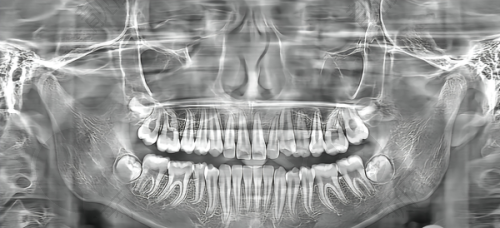

暨南雅皓口腔采用国内外多种精良的种植牙技术和设备。比如数字化导航种植、即刻种植等,这些技术可以提高手术的成功几率和患者的舒适度。医院还引进了齐全的口腔医疗设备,像CBCT全景机,拍片更清晰;显微根管仪,治疗更稳准;数字化种植导板,种牙更安心。这些设备为种植牙手术提供了高精度的数据支持,让种牙过程更加精细、安心。